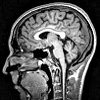

MRI of the brain.

МРТ головного мозга. Очень информативный метод сканирования, который можно использовать для диагностики мельчайших структурных изменений в мозге. Он используется для выявления структурных отклонений, травматических повреждений и патологических структур различных типов (опухоли, кисты, кровоизлияния ). МРТ головного мозга позволяет оценить структуру нервов и кровеносных сосудов, особенно вокруг орбиты и внутреннего слухового прохода. Возможна спектрография и составление трехмерной модели мозга в целом или сосудистого русла и нервов. Согласно заявлению, используется контрастное вещество.